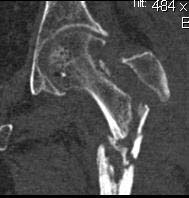

Re: Несращение проксимального отедла бедра, дефект головки

Вот еще снимки после и КТ.

Re: Несращение

кт